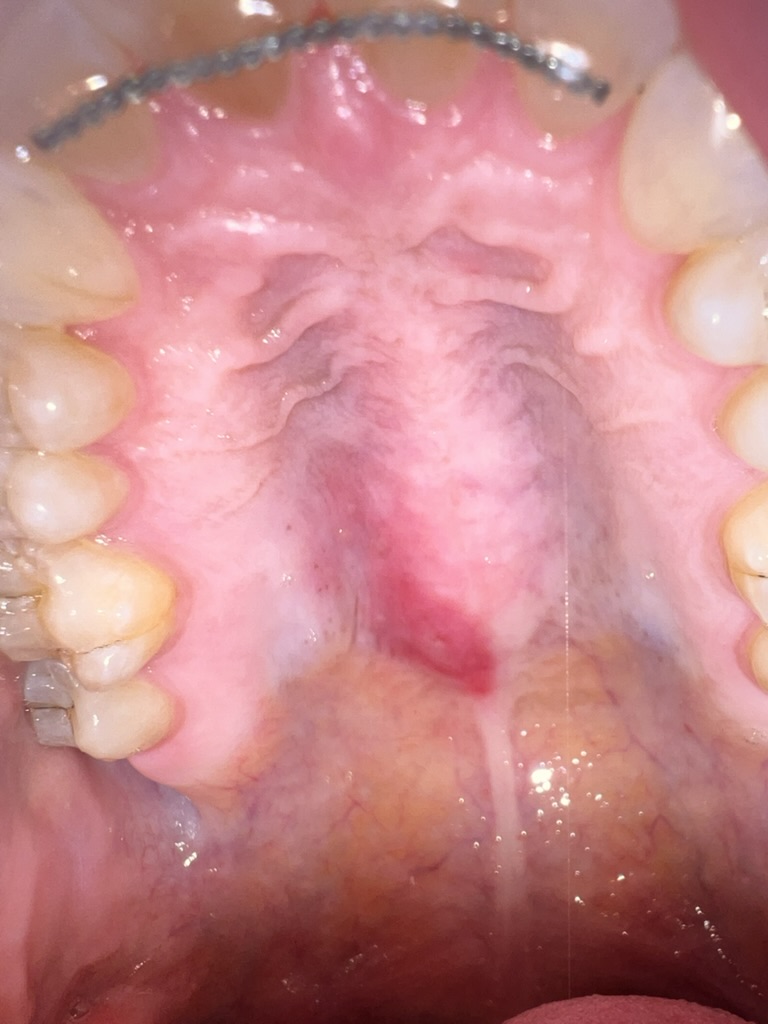

May is lupus and lyme awareness month! I always have a hard time in May, because I want to get awareness out about both. Both of these diseases mimic other things, including each other, which makes it so difficult to get a correct diagnosis. More than that though, half the time, there are no visible symptoms and you end up struggling while feeling alone. I have always been so fortunate to have a good support system and one that truly understands that just because I look well does not mean that I feel well. I am so truly grateful for that. This month there will be extra blog posts while we focus on these two diseases, but let us start with some of the symptoms that are visible. Things that I always assumed were normal and are very much NOT NORMAL! I cannot stress that enough through here and my instagram page. If you do not feel normal, it is not normal. Trust yourself, trust your gut, and trust your instincts.